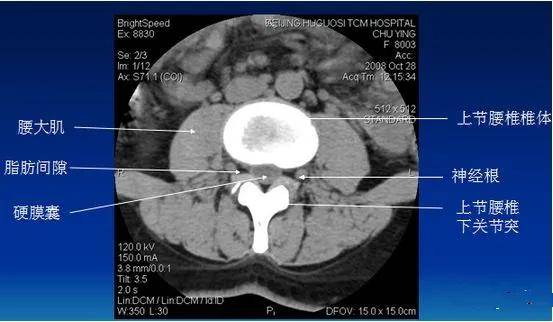

CT检查

CT检查密度分辨率高 , 无影像重叠 , 易于发现微细骨质破坏 , 对影像重叠或解剖结构复杂部位的显示优于常规X线平片 。 CT平扫可以清楚显示椎间盘突出的部位、大小、形态和神经根、硬脊膜受压的情况 , 同时还可显示黄韧带肥厚、小关节增生、椎管和侧隐窝狭窄等情况 。 突出的椎间盘有无钙化 , 一般也需要CT检查明确 。

文章图片